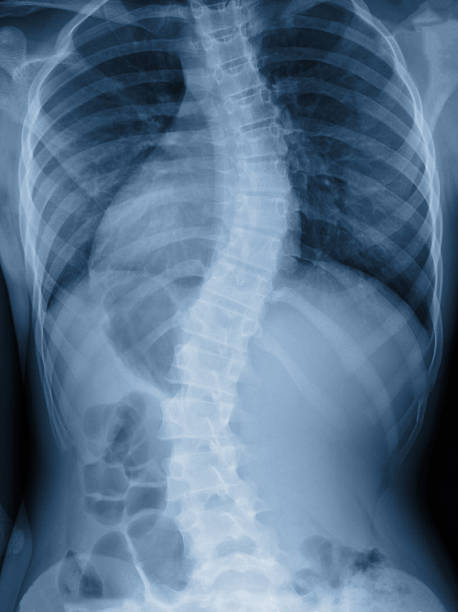

척추 측만증은 척추의 곡선이 비정상적으로 증가하여 등이 한쪽으로 치우치는 질환 입니다.

이로 인해 등이 비대칭적으로 변형되며 체형이 휘어지게 되는데요.

척추 측만증은 통증과 불편감을 유발할 뿐만 아니라 심각한 경우에는 신경 손상과 호흡 기능 저하를 초래할 수 있습니다.